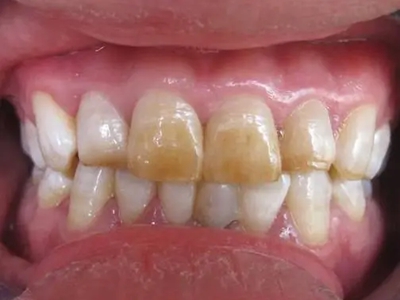

牙齿

缺损 · 发黄

牙釉质发育不全牙齿发黄缺损图

牙釉质发育不全发展到严重程度时,牙釉质表面呈棕黄色,表面有褐色凹陷,并且导致牙釉质大面积缺损,部分牙齿甚至有牙尖缺损。